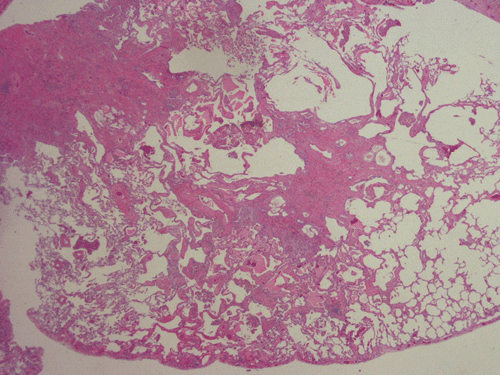

At scanning magnification (Panel A), the lung parenchyma is replaced by some coalescing fibrous nodules. The degree of involvement is variable at different fragments (Panel B and C). In the less affected areas, there are some fibrotic thickening of the septa (Panel C). In some areas, the changes are minimal and the pleural appear to be uninvolved (Panel D and E). In low to medium magnifications, these nodules of fibrosis contains a large number of hemosiderin laden macrophages (Panel F and G) admixed with fibrous tissue. The diagnostic tissue, however, is present in areas with increased cellularity. In these areas, there is a background of cells with a moderate amount of cytoplasm and bland nuclei. Some of these nuclei have kidney shape (arrow in Panel H). In some areas, many of the nuclei have a deep nuclear groove that resemble a coffee bean (arrow in Panel I). In the third type of areas, the nuclear grooving is not distinct (Panel J). Prominent eosinophilic infiltrations are almost always present. Immunohistochemistry on CD1a revealed many positive cells (Panel L). Also present in the specimen are multiple small blood vessels with thickened intima (Panel K). A Movat pentachrome stain demonstrates an internal elastic layer in these vessels and confirms that these are arteries (Panel M and N).

In the early stage of PLCH, there are interstitial infiltrates composed of LCs, lymphocytes, macrophages, eosinophils, plasma cells and fibroblasts 4. The infiltrates enlarge to form nodules centered on the small airways. Brown pigmented macrophages (smokers macrophages) are present in and around the nodules. Eosinophils tend to localize at the innermost layer of the nodules, where LCs can be most easily found in the thickened interstitium. Associated patchy interstitial and airspace organization or respiratory bronchiolitis may be present. Other smoking related changes are also common. Cavitation often occurs within the nodules which represents either an airway remenant or de novo cavitation as the inflammatory infiltrate enlarges. There is centripetal replacement of the nodules by fibroblasts which produce the classic stellate lesions of PLCH. As the disease progresses, the number of nodules, cavitary granulomas and fibrotic scars increase in number.

In the end stage, the exhausted lesions are predominantly fibrotic and largely depleted of LCs. In some regions, the fibrosis may surround cystic spaces of variable diameter to form large areas of honeycombing. This is especially predominant in the upper lobes. In cases where parenchymal scaring is present, the pulmonary function will be largely compromised. At this stage, both pulmonary function tests and radiologic findings may suggest diffuse lung disease, but biopsy will show stellate fibrotic lesions centered on the terminal airways with no identifiable interstitial inflammation. Pulmonary vasculopathy (in areas of lung remote from parenchymal nodules) is also seen in late stage PLCH. Vasculopathy manifests as intimal fibrosis, medial hypertrophy or luminal obliteration involving both venules and arteries. This may account for pulmonary hypertension seen late in PLCH.